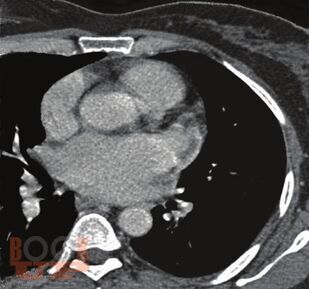

Книга посвящена одной из актуальных проблем кардиологии—тромбоэмболическим осложнениям у больных с аритмиями. Подробно обсуждаются молекулярные и генетические механизмы тромбообразования при аритмиях, клинические и инструментальные признаки внутрисердечных тромбов, а так же способы их визуализации. Приводятся данные о способах оценки риска тромбоэмболических осложнений и тактике антитромботической терапии в различных группах больных с аритмиями. Отдельно освещаются вопросы антитромботической терапии в сложных клинических ситуациях — при хирургических операциях, в случае обострения ИБС, при беременности, при проведении катетерной деструкции. Поводом для выхода второго издания книги послужило появление представителя нового класса антитромботических средств — дабигатрана этексилата, в связи с чем международное кардиологическое сообщество поменяло рекомендации по профилактике тромбоэмболических осложнений у больных с аритмиями. Для кардиологов (в том числе интервенционных), терапевтов, студентов медицинских вузов.